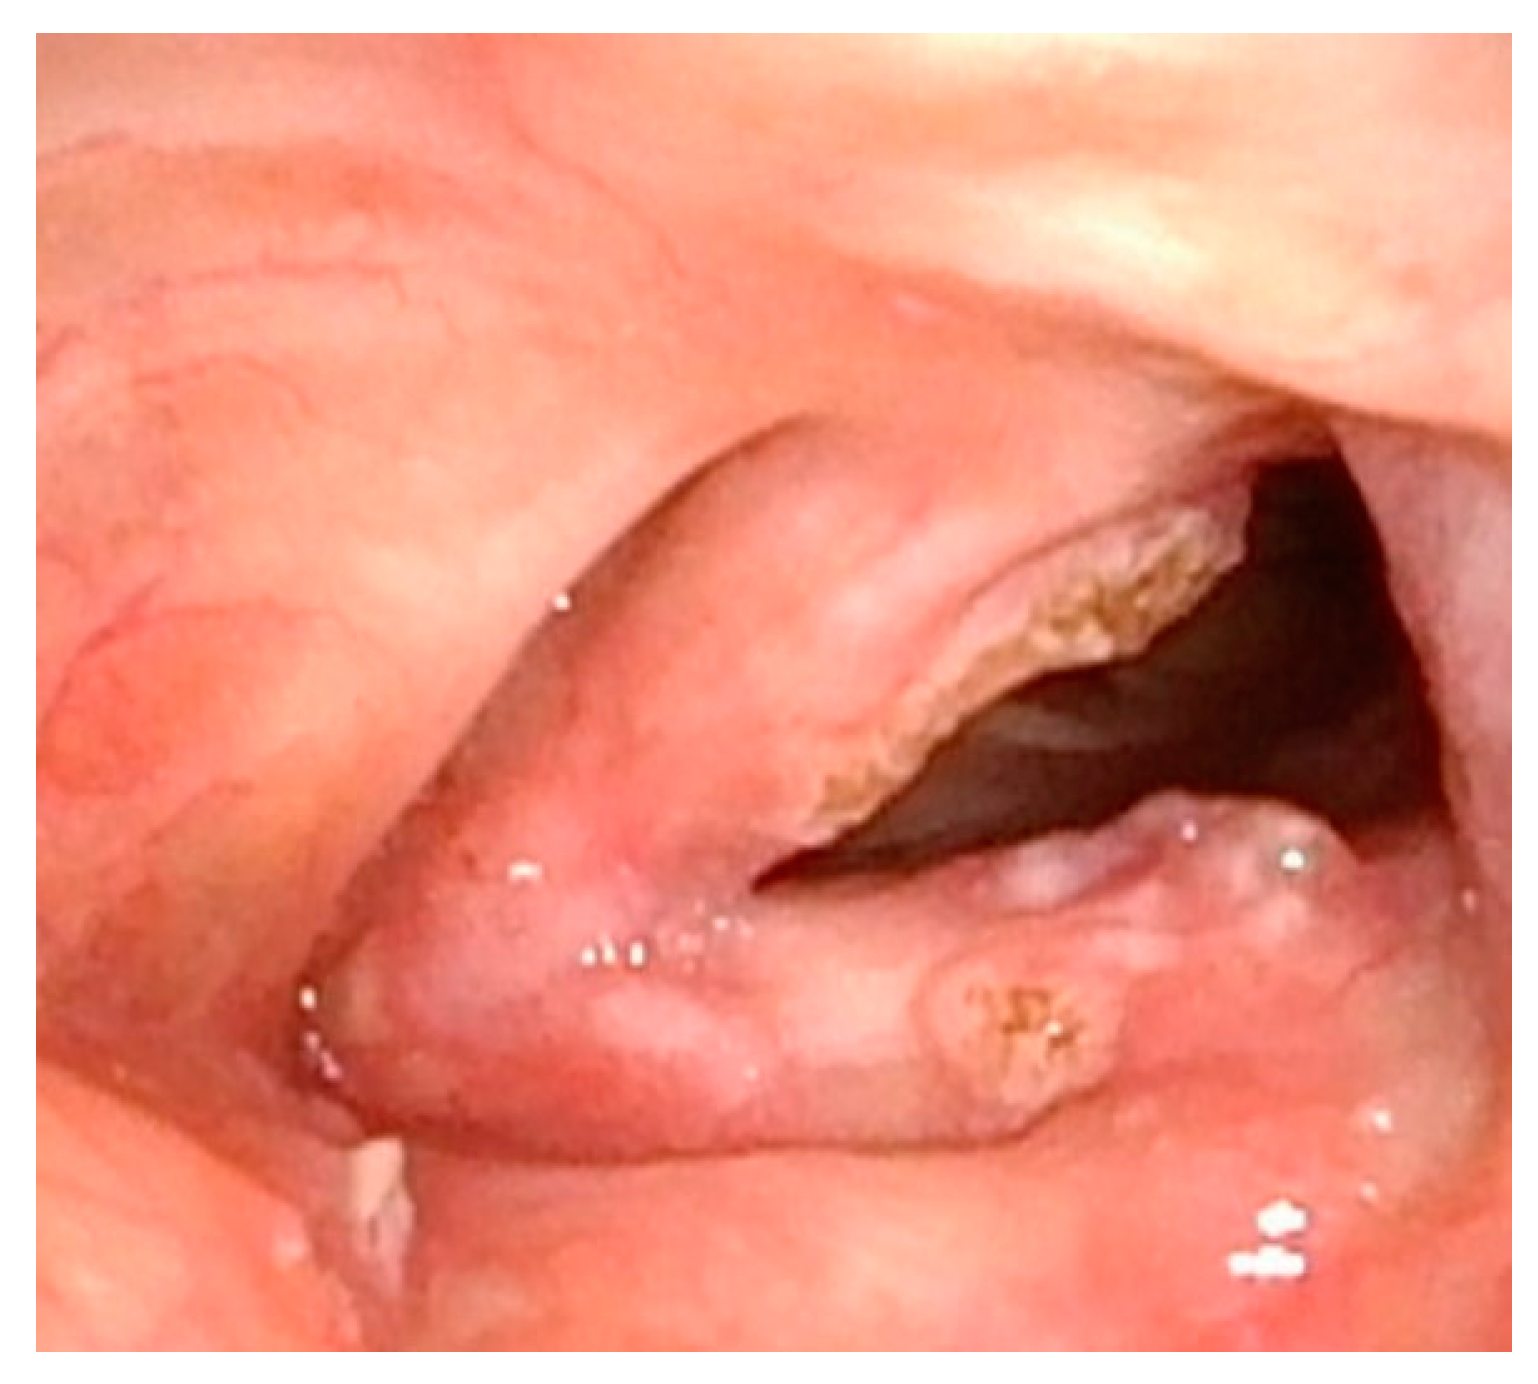

Although less common, care must also be taken not to disrupt the mucosa along the entirety of the posterior commissure. Should this occur, a patient is at great risk of developing posterior glottic stenosis (Figure 4). This should also be treated similarly to the anterior glottic web with midline lysis of the scar and injection of steroids, and dilation should always be performed in these cases (Figure 5). The combination of anterior or posterior glottic stenosis in the setting of a patient with papillomas can lead to significant airway obstruction and should be avoided in all cases with careful surgical attention (Figure 6).

Figure 4.

Significant papillomatous growths throughout supraglottis and severe posterior glottic web.

Figure 5.

Two months post-op after lysis of posterior glottic web and ablation of papillomas. Web has significantly improved, and there is already regrowth of papillomas.

Figure 6.

Significant posterior glottic web with papillomas causing near-complete obstruction of the airway.